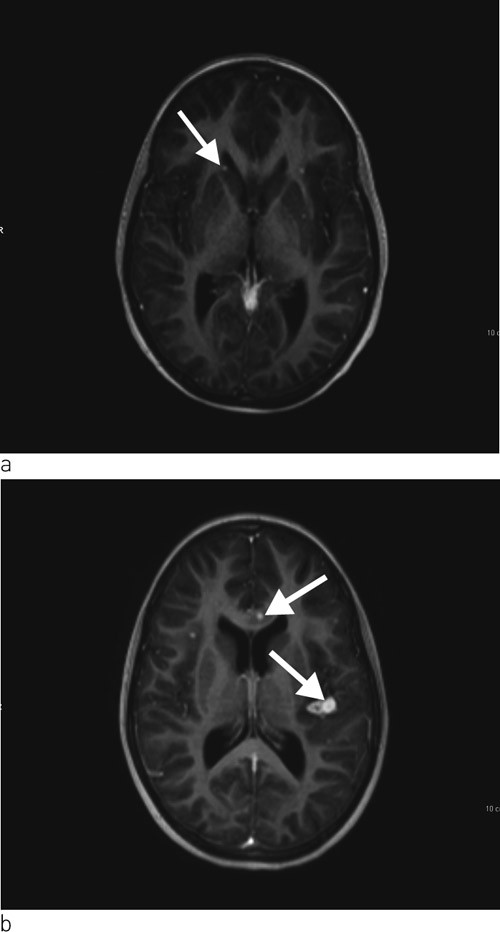

Ei veke etter innlegging var jenta klinisk dårlegare. Ho var kvalm og hadde svært redusert matlyst. Vi starta difor med intravenøs væsketilførsel og ernæring. Det vart tatt indusert sputum og gastrisk aspirat til direkte mikroskopi, PCR og dyrking med tanke på Mycobacterium tuberculosis. Vi rekvirerte også ein Quantiferon-TB Gold test. Dagen etter vart ho spinalpunktert, og vi fann leukocyttar 444 · 10⁶/l (< 3,0 · 10⁶/l), 80 % polynukleære og 20 % mononukleære, glukose 3,2 mmol/l og protein 0,31 g/l (< 0,50 g/l). På mistanke om miliær tuberkulose med meningitt starta vi med standard antituberkuløs behandling med isoniazid, rifampicin, pyrazinamid og etambutol samt pyridoksin. Dagen etter vart det i tillegg starta med intravenøs cefotaksimbehandling. Tre dagar seinare vart det gjort MR av cerebrum, som viste multiple små kontrastladande lesjonar i hjerneparenkymet, dei fleste i overgangen mellom grå og kvit substans, og i tillegg ein lesjon i basalgangliene på venstre side (fig 3a). Det var minst 16 lesjonar supratentorialt og tre infratentorialt, og den største målte 5 mm i diameter. Det vart gjort ekkokardiografi som viste normale forhold. Det vart ikkje påvist antistoff mot humant immunsviktvirus (hiv).

Tuberkuløs meningitt vil vanlegvis føre til forhøya proteinnivå i spinalvæska. Glukosenivået i spinalvæska kan vere normalt tidleg i forløpet av tuberkuløs meningitt, men er oftast lågt i seinare stadium. Vår pasient hadde ikkje låge glukoseverdiar og hadde normalt proteinnivå i spinalvæska. På grunn av den diagnostiske uvissa fekk jenta i tillegg behandling med cefotaksim. Funna på MR cerebrum kunne passe med tuberkulom, men kunne også gje mistanke om metastasar eller septiske emboliar. Det vart difor gjort ekkokardiografi for å utelukke endokarditt.

På grunn av usikker diagnose og komplisert sjukdom vart barnet dagen etter MR-undersøkinga overført til eit anna universitetssjukehus. Vi fekk så svar på Quantiferon-TB Gold som var 5,17 IU/ml (< 0,35 IU/ml). Augelege fann at jenta hadde korioretinale infiltrat bilateralt. MR av abdomen med kontrast viste hepatosplenomegali utan fokal patologi samt forstørra lymfeknutar i leverhilus og paraaortalt. 13 dagar etter overføring kom det melding om positiv polymerasekjedereaksjonstest (PCR) for M tuberculosis-komplekset i indusert sputum. Ei veke seinare vart det stadfesta vekst av M tuberculosis i indusert sputum og i spinalvæske. Stammen var sensitiv for alle testa medikament. Etter 14 dagar vart jenta overført til lokalsjukehuset. Røntgen av thorax etter to månaders behandling viste markert tilbakegang av lungefortettingane. Samstundes vart det tatt ein kontroll-MR av cerebrum som viste at dei intracerebrale lesjonane hadde auka i storleik og at det var fleire nytilkomne lesjonar (fig 3b). Jenta var framleis innlagt i avdelinga. Ho hadde ingen nyoppståtte nevrologiske symptom eller utfall. Visuelt framkalte potensial (VEP), som er ein spesifikk test av nervus opticus, vart undersøkt tidleg i behandlingsforløpet og etter åtte veker. Funna ved desse undersøkingane var normale.

Dei intrakraniale lesjonane auka i storleik etter to månader med behandling, og det hadde tilsynelatande oppstått nye lesjonar. Dette fenomenet er skildra i litteraturen (6). Årsaka er ikkje godt kjent, men representerer sannsynlegvis ein immunrespons på frisette antigen frå M tuberculosis. Slik paradoksal auke i tuberkulom utgjer ikkje indikasjon for å endre behandlingsopplegg med mindre pasienten har nevrologiske symptom eller utfall (6).